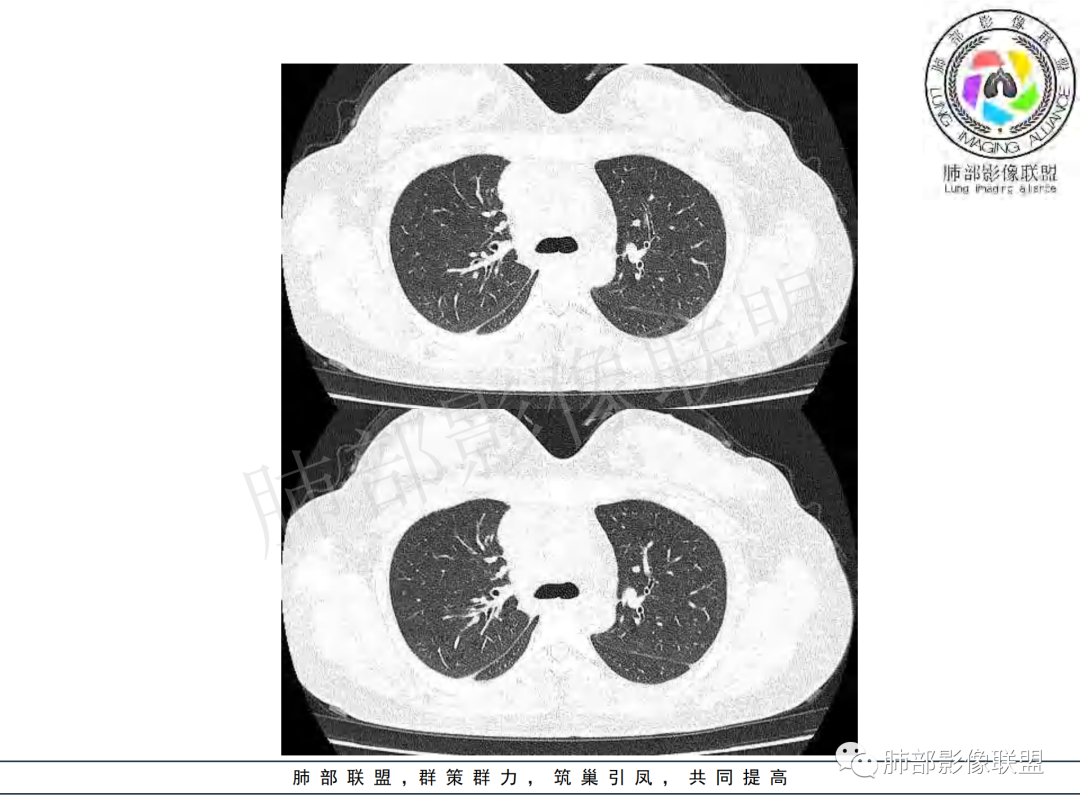

年龄和病史比较符合结核,但是中叶支气管好像堵塞了,管腔有新生物,恶性肿瘤也不能排除,做一个支气管镜应该能确诊

支气管腔内有占位,肺门区病灶和胸膜结节明显强化,淋巴结环状强化为主,部分明显强化,年轻女性,首先考虑结核,鉴别腺癌

女性,20岁。高热、畏寒。右肺上叶近肺门区不规则肿块,周围斑点、片小结节影伴肿大淋巴结,肿块包绕并突入右主支气管腔内,增强后肿块不均匀强化,淋巴结环形强化中心低密度,考虑结核。

本例患者,年轻女性,慢性病程,多次抗感染治疗效果不佳,实验室检查示白细胞及中性粒细胞不高,不支持普通细菌感染,虽然肺泡灌洗液X-Pert检测阴性,结合患者胸部CT结核感染亦不能排除,胸部CT主要表现为右侧肺门及纵隔淋巴结肿大,仔细观察不难发现右中间支气管内新生物凸向管腔内,增强扫描,右肺门(10R)及纵隔淋巴结(2R,4R)明显不均匀强化,内部呈不规则低密度无强化区,被周边高强化区包绕(环形强化)的特点,首先应当想到纵隔淋巴结结核诊断。淋巴结分布亦不符合肺部恶性肿瘤迁徙途径。